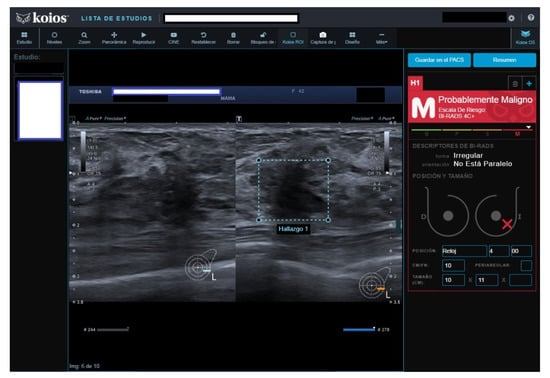

All four B2 cases had benign pathology results; a biopsy was performed for the following reasons after MCBP revision (B2 should not be biopsied): One had been core-biopsied 2 years previously, but due to the suspicious nature of the image, a wider vacuum-assisted biopsy was performed (Figure 2). The second had an unsuspicious scar from a previous malignant lumpectomy (micropapillary Ca), but because the patient presently had a cytologic papilloma diagnosis for nipple secretion, a new biopsy was performed. The third had a suspicious image from a previously benign biopsy (not performed at our institution) and previous studies with no obvious changes. Our MCBP recommended a new biopsy. The fourth had a suspicious mammography finding that was correlated with a benign-appearing BUS image. KOIOS reported cases one, two, and four as KPM and case three as Kpb.

Figure 2.

Suspicious image rated B2 by reader because of prior benign core biopsy (usual hyperplasia) and absence of change; rated KPM by KOIOS. Our multidisciplinary committee indicated a new and wider biopsy that was performed with US guidance and vacuum assistance. Pathology reported adenosis.